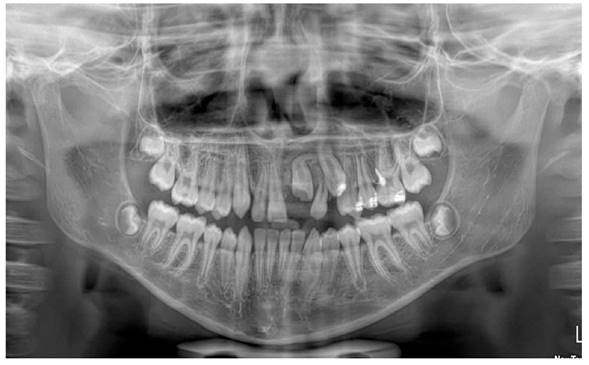

Al examen clínico inicial (Figura 1), se aprecia ausencia de unidad dentaria superior; y al examen radiográfico inicial (Figura 2), la radiografía panorámica muestra una falta de erupción del incisivo central superior izquierdo permanente (UD 21), con desviación hacia el mesial de canino superior izquierdo permanente (UD 23) sin erupcionar, en íntimo contacto con la raíz del incisivo lateral izquierdo permanente (UD 22). Se puede apreciar presencia de zona radiolúcida en tercio incisal de la UD 21, presuntamente asociada a un defecto del desarrollo del esmalte, específicamente hipoplasia de esmalte. Presenta un patrón de exfoliación dental acorde a la edad en el sector inferior, etapa 8 de Nolla.

No se evidencia presencia de dientes supernumerarios ni agenesias dentales. En las imágenes axiales y frontales de la tomografía axial computarizada, puede observarse la falta de erupción de la UD 21 y su estrecha proximidad con la UD 23, así como la dilaceración radicular de la UD 22 (Figura 3). Al examen extraoral, se observa perfil facial ligeramente convexo; y al examen bucal intraoral, se aprecia overjet y overbite normales, sin apiñamiento, líneas medias dentales coincidentes con la línea media facial, clase I molar.

En un estudio realizado en pacientes con dientes traumatizados, se detectaron anomalías dentales en los dientes permanentes sucesores en 21 pacientes, en 26 dientes y 28 anomalías. Lo más frecuentemente encontrado fueron anomalías del proceso eruptivo, después la hipoplasia del esmalte y las manchas blancas. Si el traumatismo era en menores de 36 meses, se encontró que el porcentaje de anomalías era más frecuente. Las luxaciones intrusivas y extrusivas se vincularon con alteraciones clínicas en los dientes permanentes sucesores. Se señala en esta investigación el riesgo de anomalías dentarias posterior a un trauma en dentición primaria 15. En el presente caso reportado, al analizar la radiografía panorámica, se observó una imagen en la zona del tercio incisal del incisivo central superior izquierdo permanente, que al erupcionar se pudo evidenciar que era una hipoplasia dental. Asimismo, al realizar radiografías posteriores, se apreció una dilaceración radicular en el incisivo lateral del mismo lado (Figura 7). De Amorim et al. 16 encontraron, entre un grupo de 815 dientes primarios traumatizados, que las secuelas más comunes observadas en los dientes sucesores fueron decoloración del esmalte, hipoplasia dental, y dilaceración radicular y de la corona. Todos estos datos coinciden con las manifestaciones bucales encontradas en el presente reporte de caso.

En el presente caso, se encontró una dilaceración en el incisivo lateral, la cual se define como una anomalía dental caracterizada por una desviación brusca en el eje longitudinal de un diente. Puede ocurrir en la corona, entre la corona y la raíz, o en la raíz. A pesar de no ser tan prevalentes, los incisivos superiores retenidos que presentan dilaceración radicular representan un reto en el diagnóstico y tratamiento para el clínico. La dilaceración se observa como una deformidad dental con una angulación entre la corona y la raíz, que puede interrumpir la erupción del incisivo. En este reporte de caso, no fue el diente impactado (UD 21) el que presentó la dilaceración radicular, sino el diente vecino (UD 22) y el canino superior (UD 23).

Corroborando lo antes expuesto, Tan et al. 19, en su investigación sobre dientes impactados, encontraron que los incisivos centrales superiores permanentes fueron los dientes más comúnmente afectados (70,6 %). Las causas más comunes de incisivos no erupcionados fueron dilaceraciones (n = 83; 36,7 %) de los incisivos centrales superiores; anomalías del desarrollo dental (n = 22; 30,6 %), a la par de desarrollo radicular no favorable (n = 22; 30,6 %) para los incisivos laterales superiores y relación anormal diente/tejido (n = 11, 50,0 %) para los incisivos inferiores. En su mayoría, los incisivos no erupcionados tuvieron secuelas, entre las que destacó la posición ectópica/desplazamiento/rotación de los incisivos no erupcionados (46,6 %), falla de espacio (36,9 %) y desplazamiento de línea media (27,5 %). Estos antecedentes se parecen mucho a los del presente reporte de caso, en el que se encontró falta de espacio, impactación dental, trastorno en la erupción de otras unidades dentarias, presencia de anomalía dentaria tipo hipoplasia dental y dilaceración radicular.